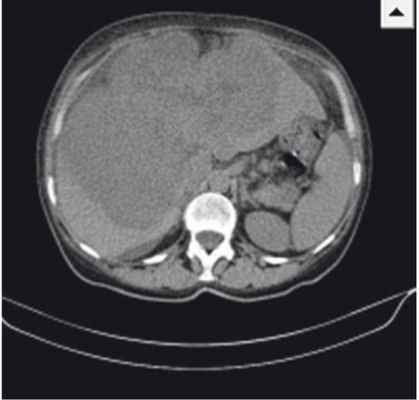

Результаты контрольной КТ от 12.05.2014: печень увеличена в размерах, деформирована, имеет крупнобугристый контур; паренхима обеих долей печени субтотально (около 70%) заменена объемным мультифокусным образованием размерами 208 × 127 × 185 мм (рост) с неровными бугристыми контурами и неоднородной гиподенсной плотности (рис.). При проведении ангиографии обнаружено, что образование активно, выраженно неравномерно, преимущественно по периферии, накапливает контрастное вещество до +130 HU с сохранением зон отсутствия контрастирования (некрозы).

Рис. Компьютерно-томографическая картина гигантской цистаденокарциномы печени. Фото авторов

При осмотре от 10.06.2014 отмечены жалобы на боли в правом подреберье, пожелтение кожи, склер, кожный зуд. Объективно: кожный покров желтушный, обычной влажности, склеры иктеричные; язык обложен желтоватым налетом, влажный; живот не вздут, мягкий, увеличен в размерах за счет гепатомегалии; печень значительно увеличена в размерах, безболезненная, плотная, выступает из-под реберной дуги на 8–10 см; стул периодически гипохоличный. В анализах крови — повышение уровня СА 19-9 до 897 Ед/мл. По данным УЗИ: вся брюшная полость, включая боковые фланки и позадиматочное пространство, заполнена свободной жидкостью с небольшим количеством мелкодисперсной взвеси — асцит; печень увеличена (краниокаудальный размер — 225 мм), деформирована, имеет крупнобугристый контур; паренхима обеих долей печени субтотально (свыше 70%) заменена объемным мультифокусным образованием с неровными бугристыми контурами размерами 218 × 151 × 193 мм; аналогичное по плотностным характеристикам образование визуализируется в S8 (20 × 22 × 22 мм), появилось новое аналогичное образование в S3 (12 × 12 мм).